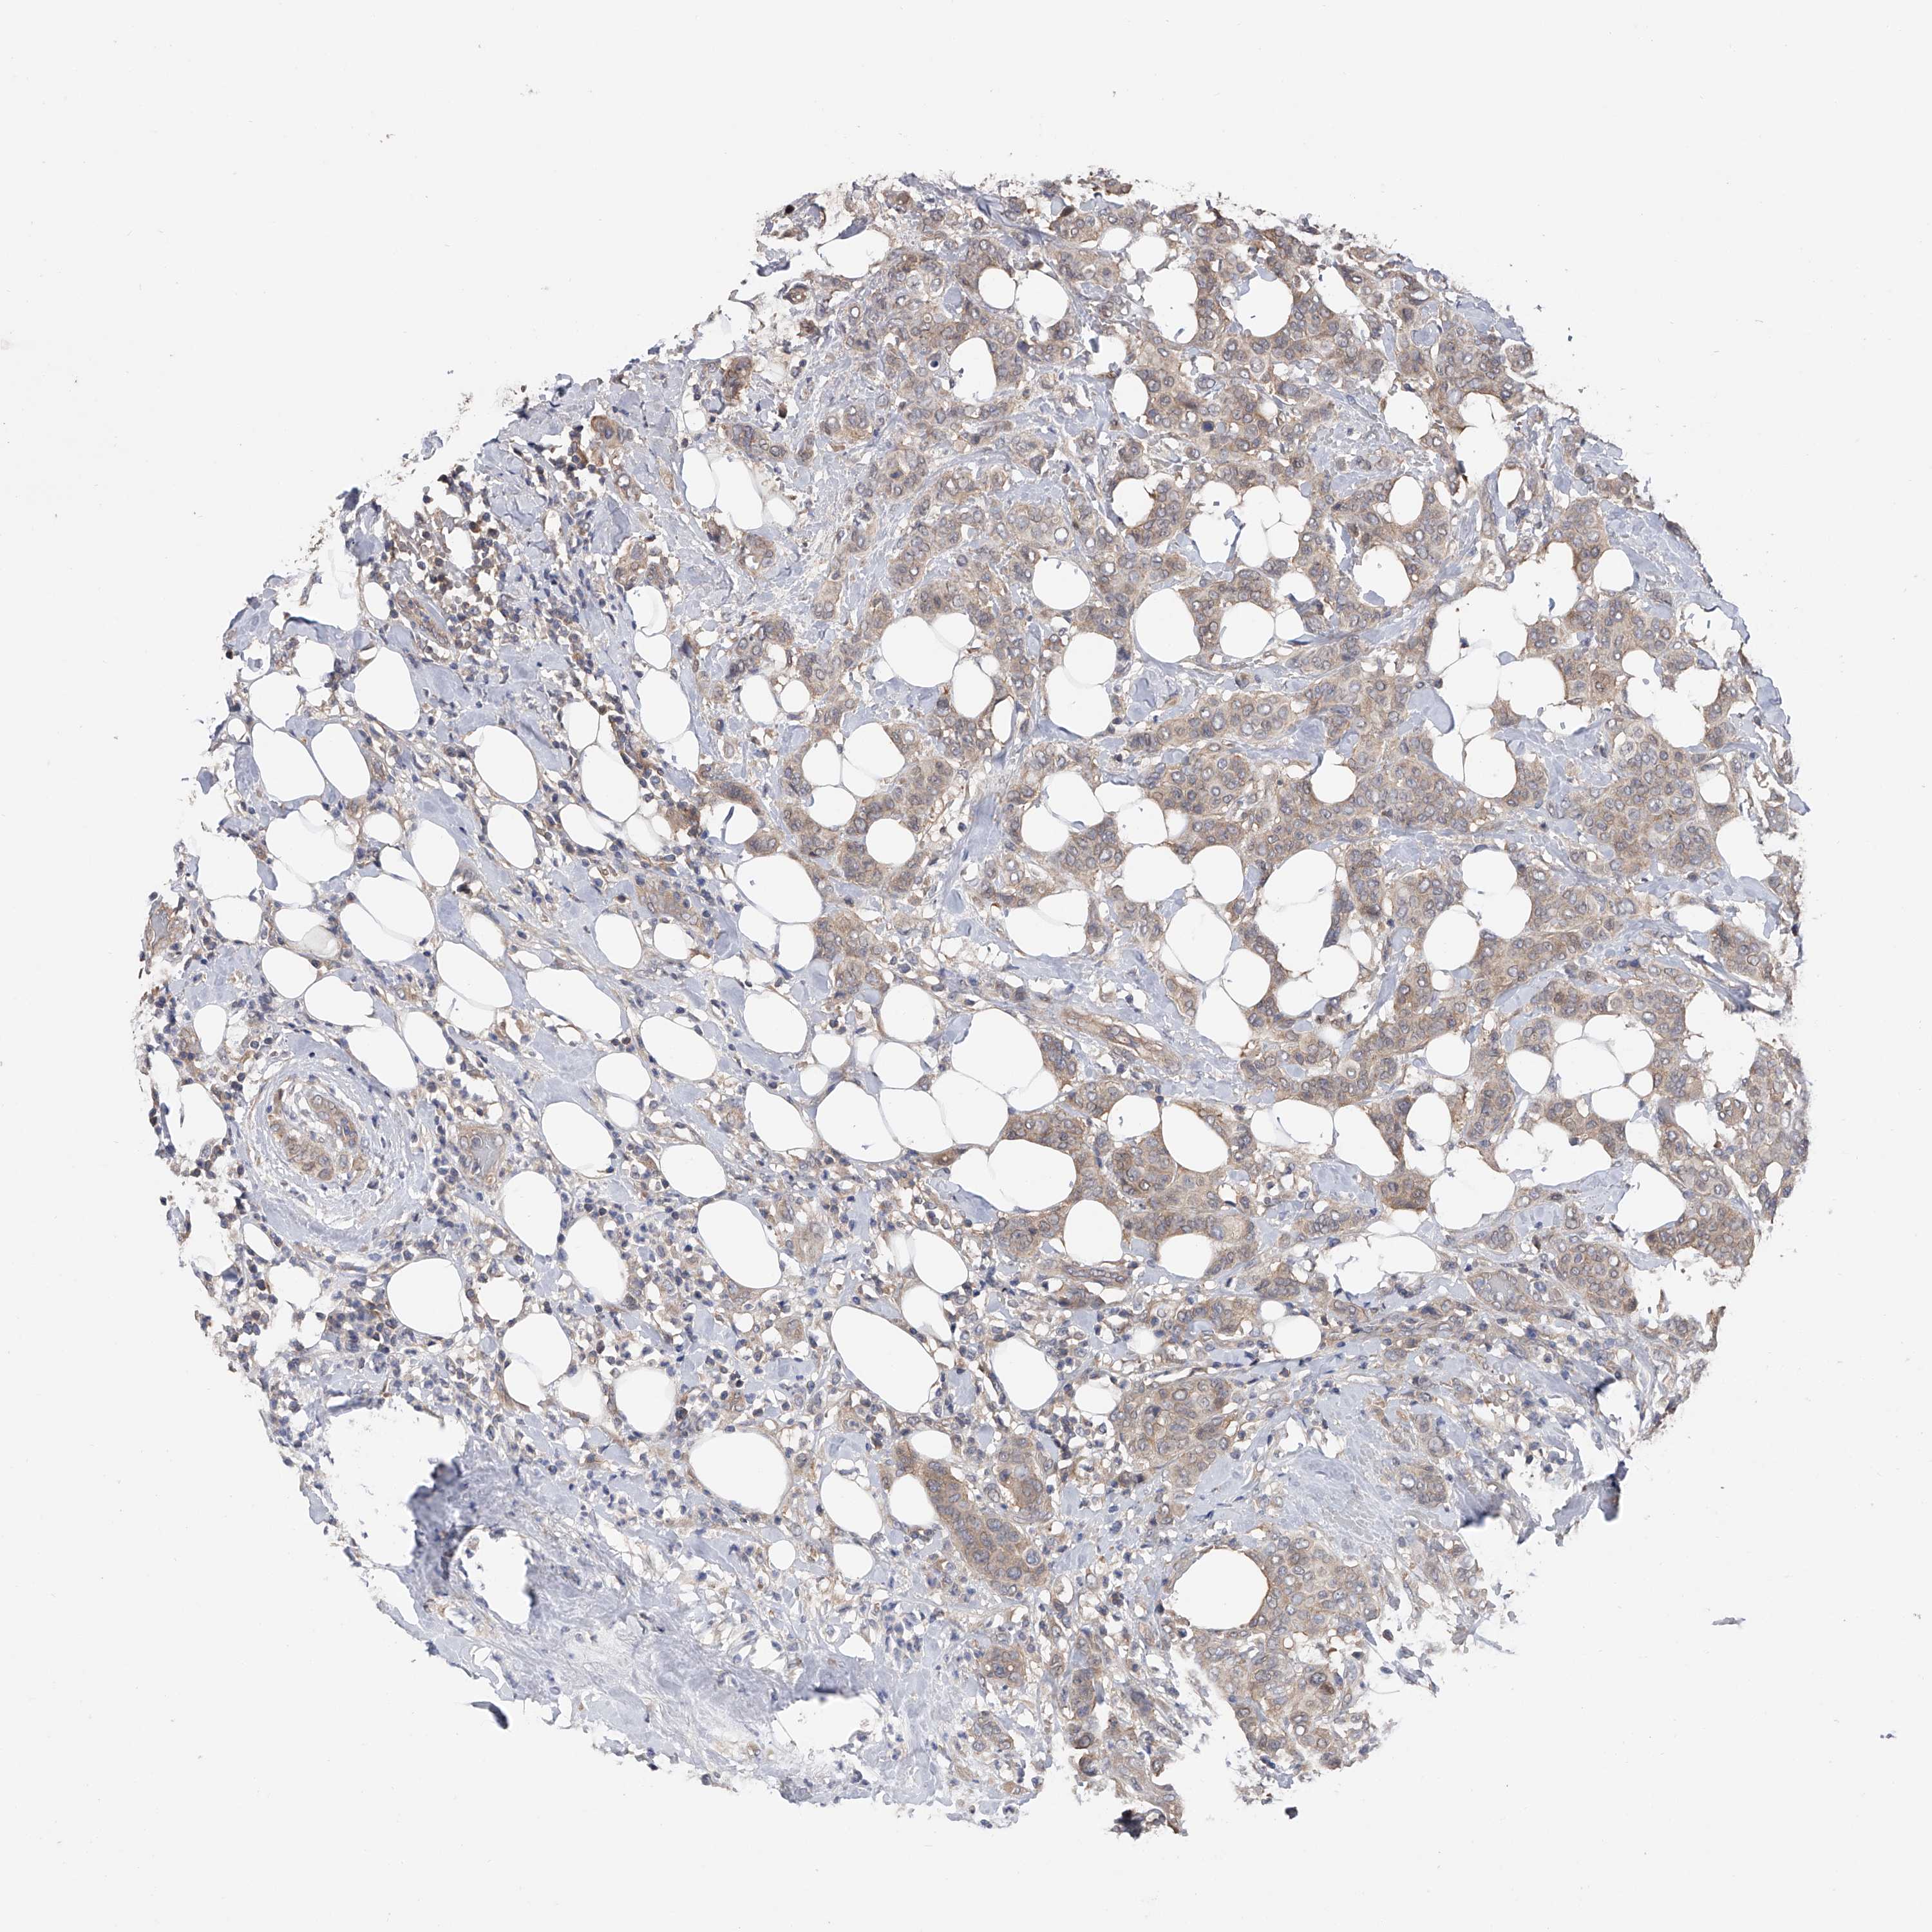

CANCER BREAST CANCER Show tissue menu

BRCA TCGA BRCA VALIDATION PROTEIN EXPRESSION